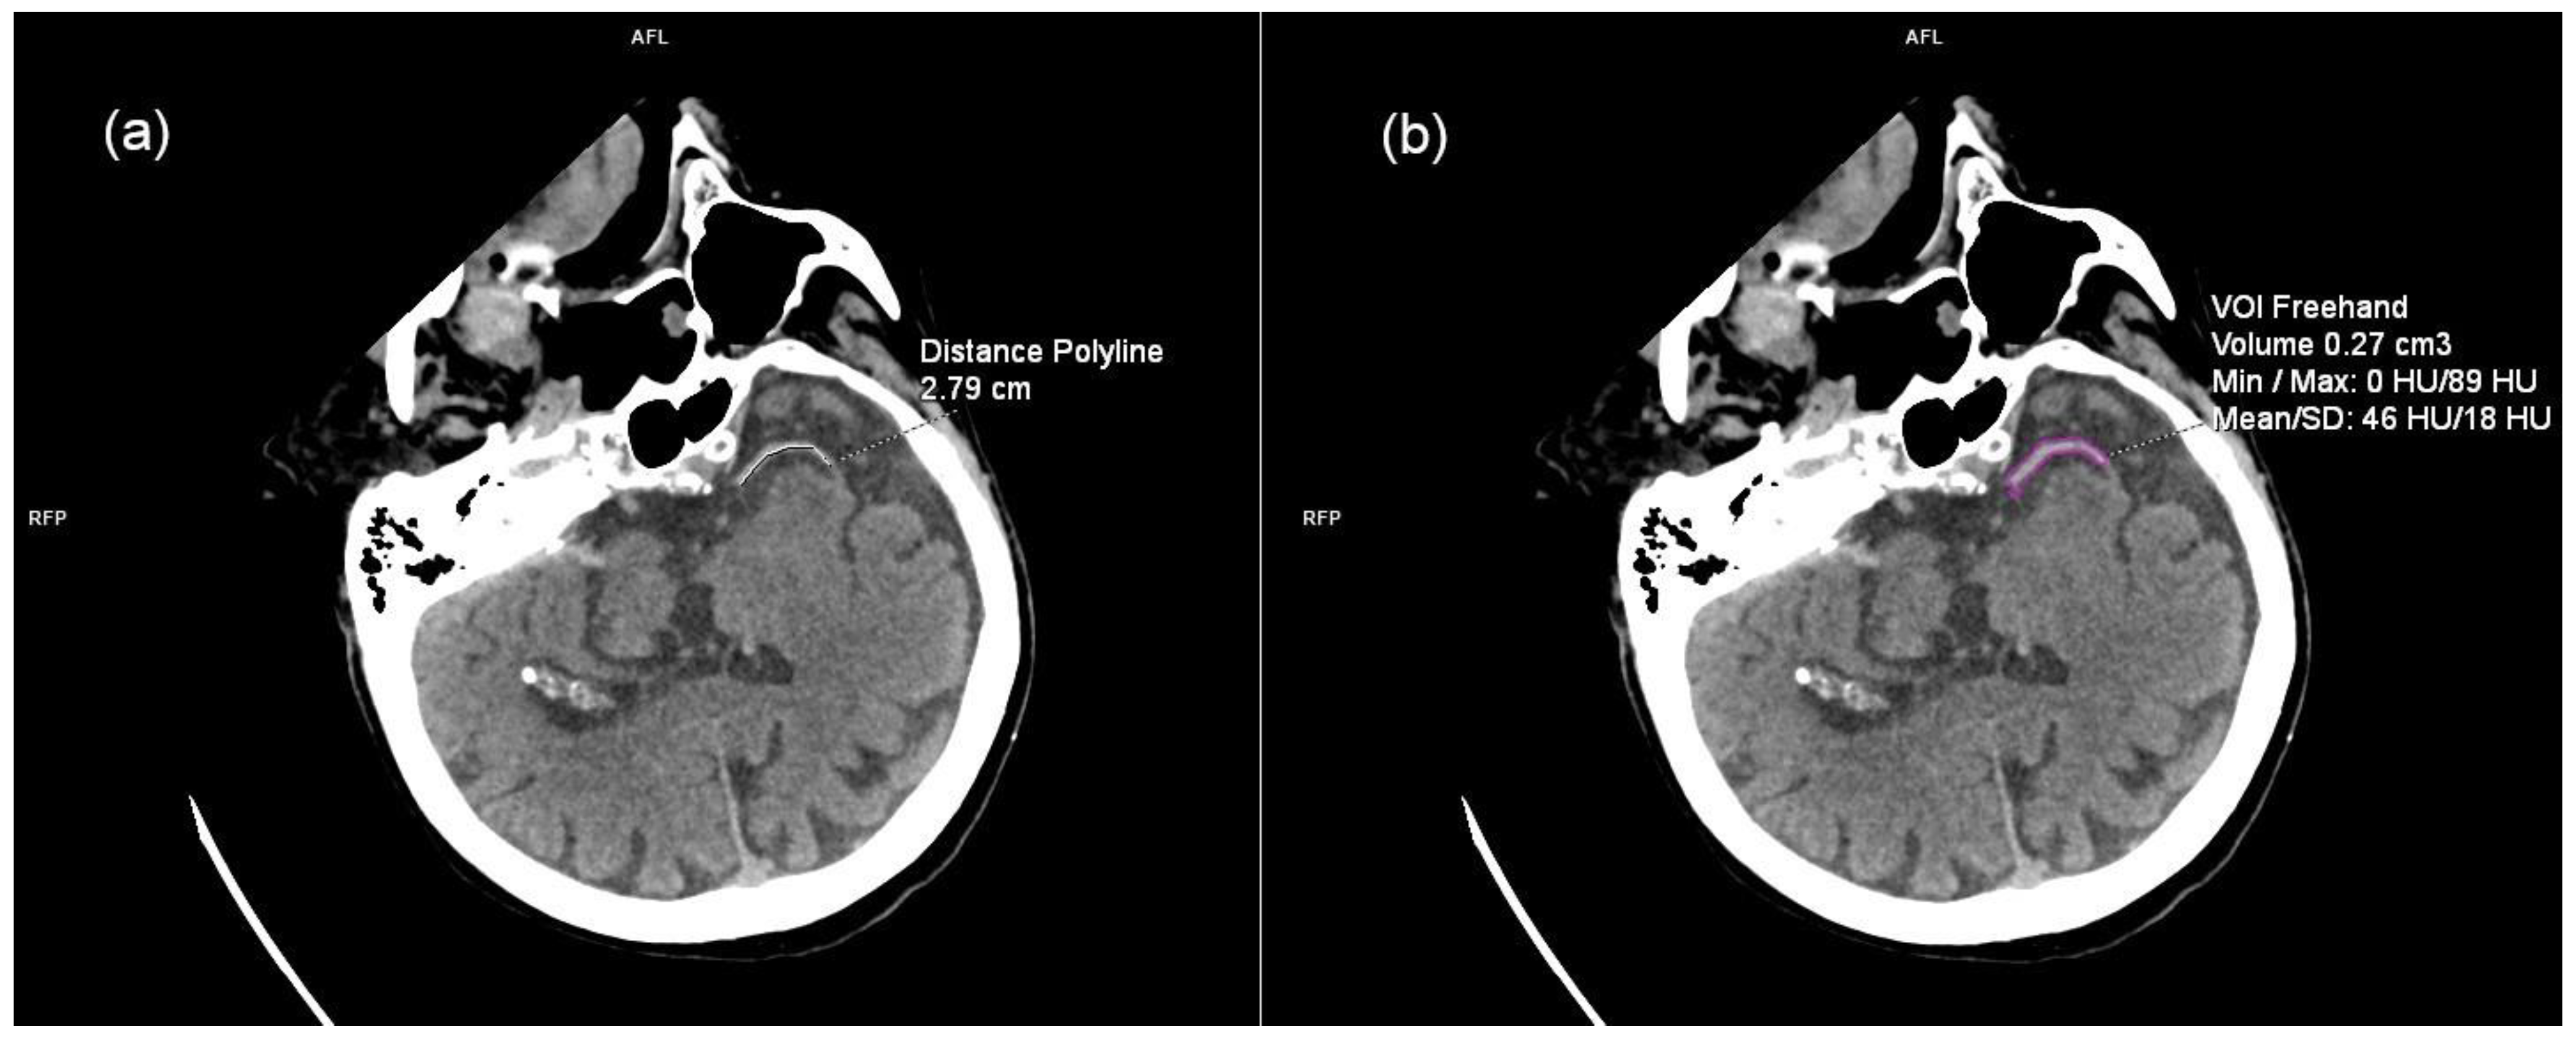

2.3. Imaging Data and Analysis